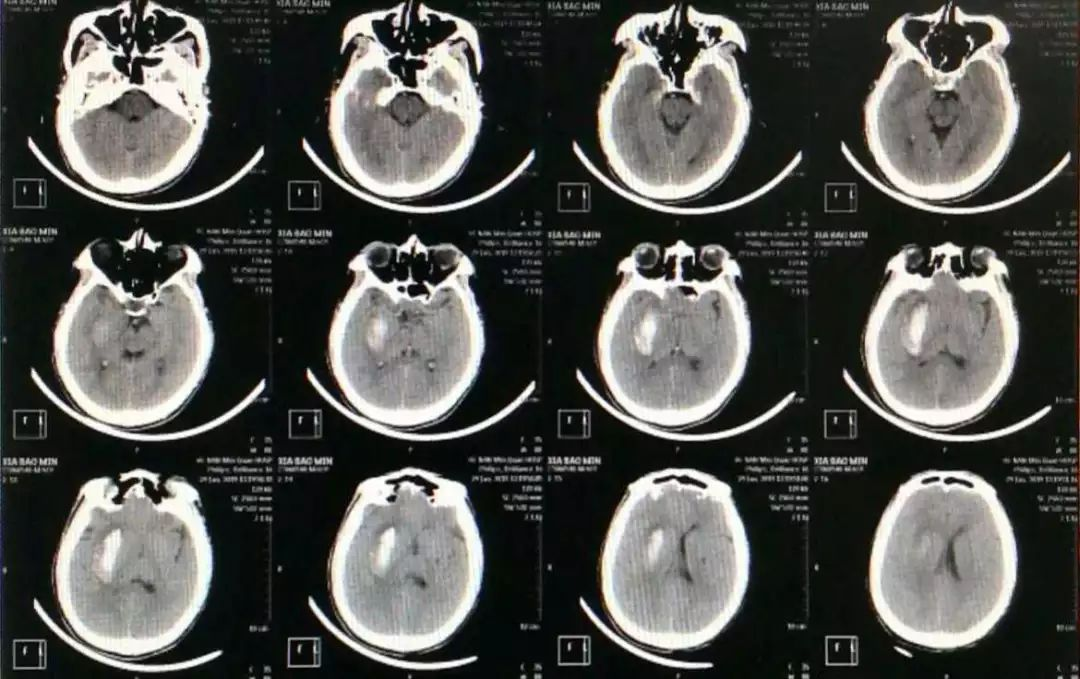

夏某,男, 岁,以“左侧肢体无力一天”入院,发病时感左侧上肢无力,持物不能,后逐渐加重,头痛,来我院后CT检查示:右侧基底节脑出血,病人意识呈嗜睡状,左侧上肢肌力0级,左侧下肢肌力3级,左侧巴氏征阳性。职业:长期从事泥瓦工,饮酒频繁。

入院时CT:

患者意识呈嗜睡状,呼之能应,能正确回答问题,遵嘱动作,给予非手术治疗,一天后患者意识加重至朦胧,诉头痛明显,左侧面部发汗异常,双侧瞳孔左=右,直径约2mm,对光反射可。

复查CT示:侧脑室、三脑室较前受压明显,血肿周围分层低密度明显

仔细观察CT片可见血肿呈分层现象